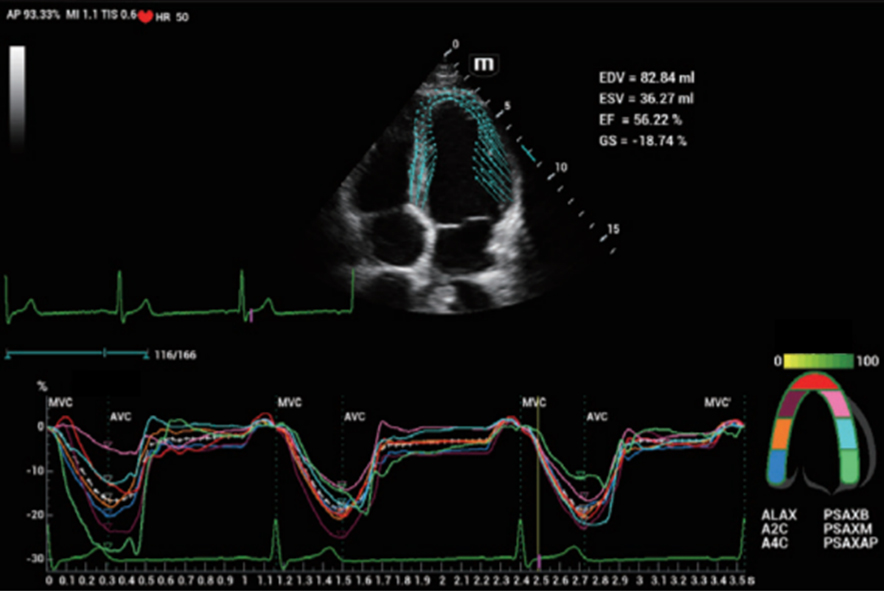

Com tecnologia ZST+

A plataformaZST+ representa um salto extraordinĂĄrio na tecnologia de ultrassom, passando da tradicional forma??o de feixe para o processamento de dados de canal. Essa inova??o revolucionĂĄria supera as compensa??es tradicionais entre resolu??o espacial, resolu??o temporal e uniformidade do tecido, resultando em uma qualidade de imagem inigualĂĄvel com infinitas solu??es de gera??o de imagens.

O Resona I9 fornece solu??es clĂnicas abrangentes para aplica??es dedicadas. Com base em percep??es aprofundadas em diferentes cenĂĄrios clĂnicos, ele oferece inova??es que fornecem aos usuĂĄrios extrema clareza, inteligĂȘncia excepcional e confian?a excepcional no diagnĂłstico.